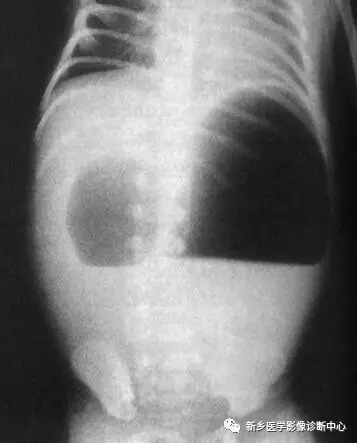

9 十二指肠闭锁

文章图片